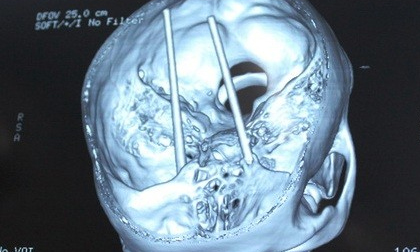

Mâu thuẫn, xuyên đôi đũa qua 2 mắt bạn nhậu

Thấy bạn nhậu bình luận và chê những hình xăm trên người mình, Tưởng dùng đôi đũa xuyên qua 2 mắt anh ta.

Nghi án thanh niên bị đối thủ đâm 2 chiếc đũa xuyên qua mắt

Khi bắt kịp anh Dũng, nhóm thanh niên này dùng 2 chiếc đũa lần lượt đâm vào hốc mắt và dí mạnh cho đến khi...